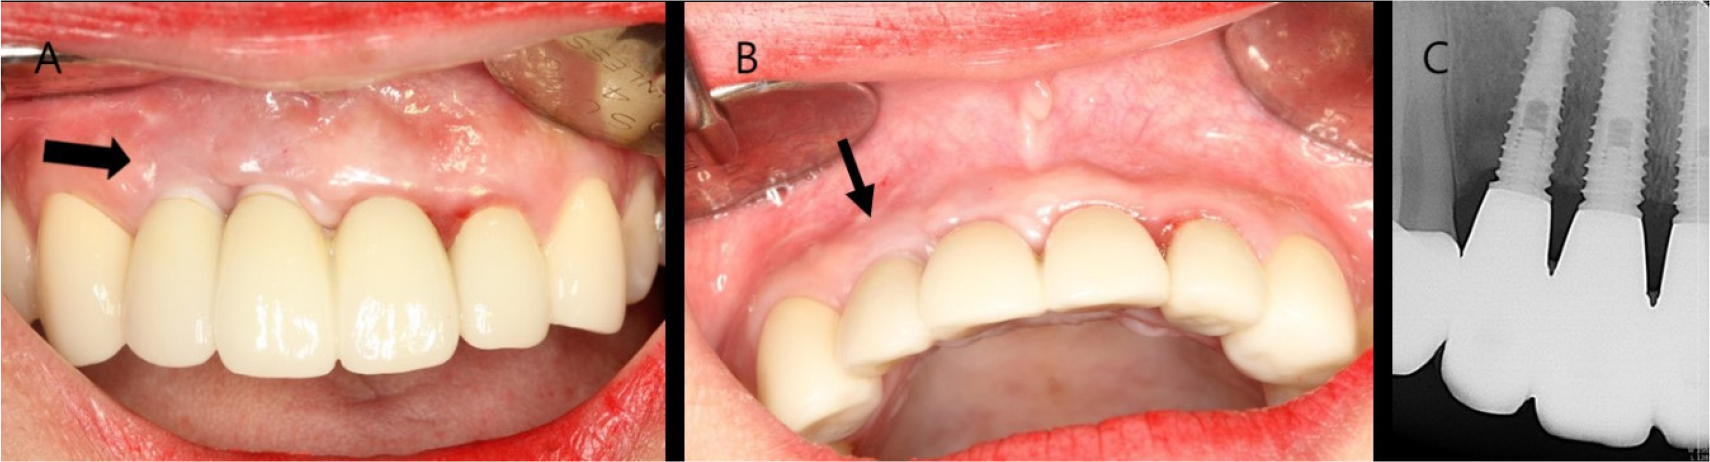

The patient was diagnosed with a facial peri-implant soft tissue deficiency of the left maxillary lateral incisor. Soft tissue grafting was planned for gingival coverage of the exposed fixture. A horizontal incision was made around the mucogingival junction, and a partial thickness flap was reflected. The metal of the shoulder part of the buccal inclined fixture was exposed. Epithelized gingival tissue was obtained from the palate. A free gingival graft was sutured on the recipient site. The stitches were removed after 2 weeks. Normal healing took place without any adverse events. Complete metal coverage occurred, but the gingival scars remained (Fig. 6). At the 3-year follow-up, the grafted soft tissue had stably maintained, and peri-implant tissues had remained healthy (Fig. 7).